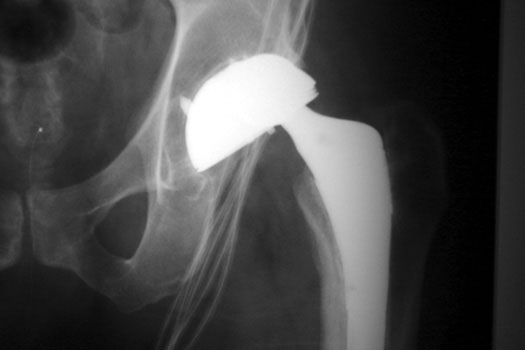

OSTEOLYSIS—Gruen zones 2 and 3, with markedly thinned femoral cortex, placing patient at risk for pathologic fracture

OSTEOLYSIS—ABOUT ACETABULAR COMPONENT GRUEN ZONE II, WITH PATHOLOGIC FRACTURE

OSTEOLYSIS

Multifocal and massive, involving Gruen zone III of acetabular cup and Grune zone 1,2, and 6 of femoral component